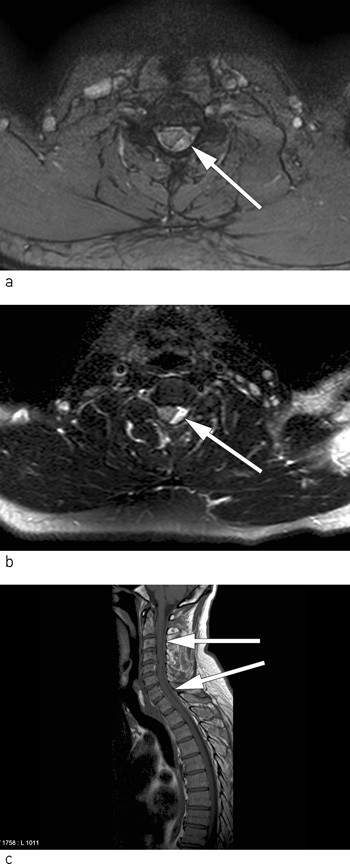

After thrombolysis the patient was placed in the Department of Neurology, and an MRI scan of the spinal cord was planned. Because of the time window for starting thrombolysis, an MRI of the spinal cord was not performed in advance. However, in the department the pareses in the right upper and lower limb increased, and it was decided to perform an acute MRI of the spinal cord and a further MRI of the brain. The MRI of the brain was still normal, but the MRI of the spinal cord showed congestion consistent with epidural haematoma located dorsally on the left side from the 3rd to the 7th cervical level. On images, the spinal cord is considerably compressed at the 4th and 5th cervical level (Fig. 2 a-c).

The patient’s symptoms and clinical findings were still perceived as a classic case of anterior spinal artery syndrome, and the haematoma discovered on the MRI images was assumed to be the cause (11). The syndrome presents clinically in the form of acute tetra- or paraparesis, impaired pain and temperature sense, rectal and bladder paresis, but preserved vibratory and proprioceptive sense. The anterior spinal artery syndrome is due to occlusion or compression of the anterior spinal artery or branches thereof (4, 10, 12).